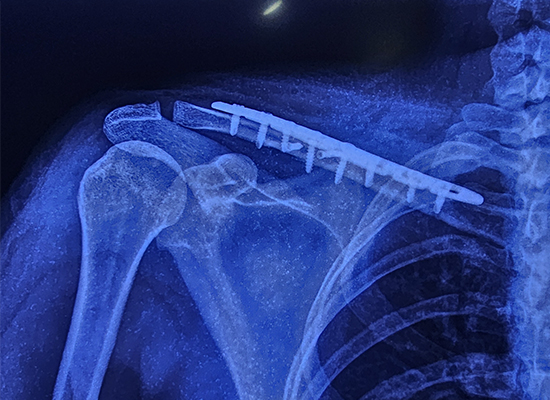

L'intervention chirurgicale impliquait l'utilisation d'une plaque de verrouillage spécialisée pour la clavicule en S, un implant avancé conçu pour assurer la stabilité dans les fractures multifragmentées. La plaque à 8 trous a été choisie en raison de son ajustement précis et de sa capacité à soutenir la fracture pendant le processus de cicatrisation. L’opération s’est bien déroulée et aucune complication n’est survenue pendant l’intervention.

Le patient est sorti 24 heures seulement après l’intervention chirurgicale, démontrant l’efficacité de l’approche thérapeutique. L'imagerie prise six semaines après l'opération a montré que la fracture était complètement guérie et que la patiente était capable de reprendre ses activités quotidiennes sans inconfort. Cette récupération rapide met en évidence les avantages de l’utilisation d’implants modernes comme la plaque de verrouillage de la clavicule S dans les chirurgies orthopédiques.

Type d'implant : Plaque de verrouillage pour clavicule en S

Taille : 8 trous, côté droit

Matériau : Alliage de titane pour plus de solidité et de durabilité

Le contour en forme de S épouse l'anatomie de la clavicule, répartissant uniformément les contraintes et empêchant le descellement ou la migration de l'implant.

La procédure s’est déroulée sans problème, sans complications nerveuses, vasculaires ou des tissus mous, et la récupération s’est déroulée sans incident.

Le patient est sorti dans les 24 heures suivant l’intervention chirurgicale avec une cicatrisation stable.